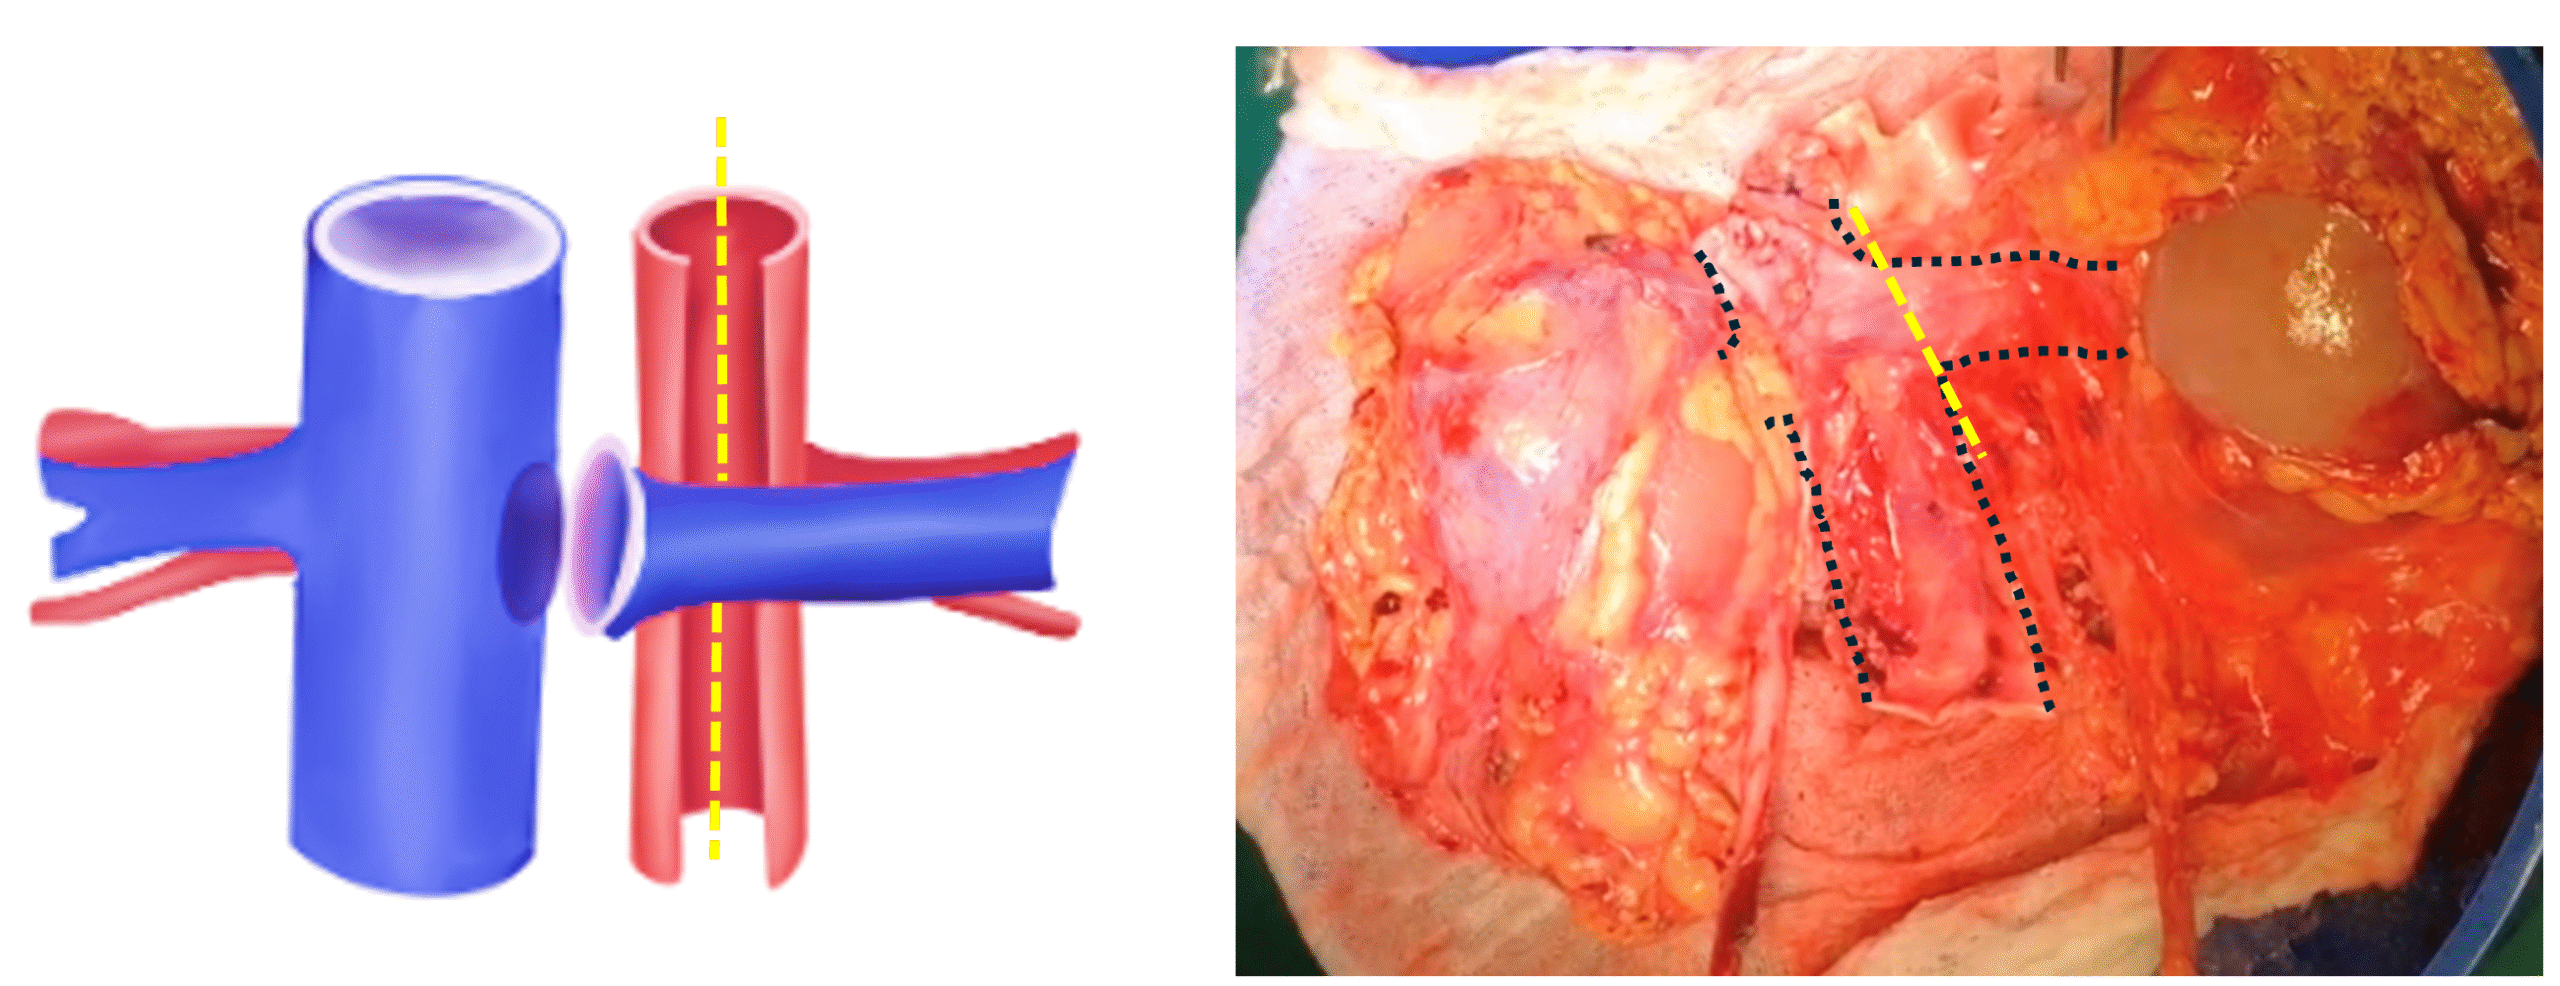

- En Bloque: Sección uréteres bajo cruce de iliacos, se recomienda marcar lateralidad con instrumental quirúrgico (Kelly recta/ curva). Sección de venas gonadales. Sección aorta y cava, caudal a nivel de cánulas. Disección a proximal, seccionando tejido retroaórtico y vasos lumbares. Disección y liberación de riñón de estructuras perirrenales, sección de VC y AA sobre nivel de hilio renal y extracción. Una vez extraídos se realiza sección de AA por línea media de su cara posterior (Figura 3) de caudal a proximal, se identifican ostiums renales. Sección de vena renal izquierda, en su llegada a VC, dejando parche de cava completo junto con riñón derecho (Figura 4).

Fig. 3. Riñones en bloque. Sección de la aorta por línea media posterior en línea punteada amarilla

Imagen 3: Riñones en bloque. Sección de la Aorta por línea media posterior en línea punteada amarilla

Fig. 4. Esquema: Sección de la vena renal izquierda a ras de VC y sección de la aorta por la mitad en forma longitudinal (línea punteada amarilla), dejando parche de aorta para ambos riñones. Foto de Riñones extraídos en bloque, línea punteada negra muestra vena cava y vena renal derecha.